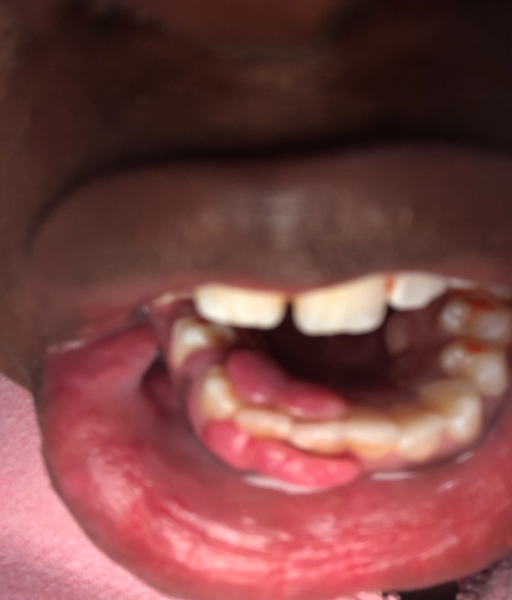

My gum is growing over my teeth

Why are my gums growing over my bottom teeth? It hurts so bad I can barely take it. I have a very hard time brushing because they bleed.They also bleed, it hurts when I eat. Sometimes I wake up in the middle of the night and have blood on my pillows...